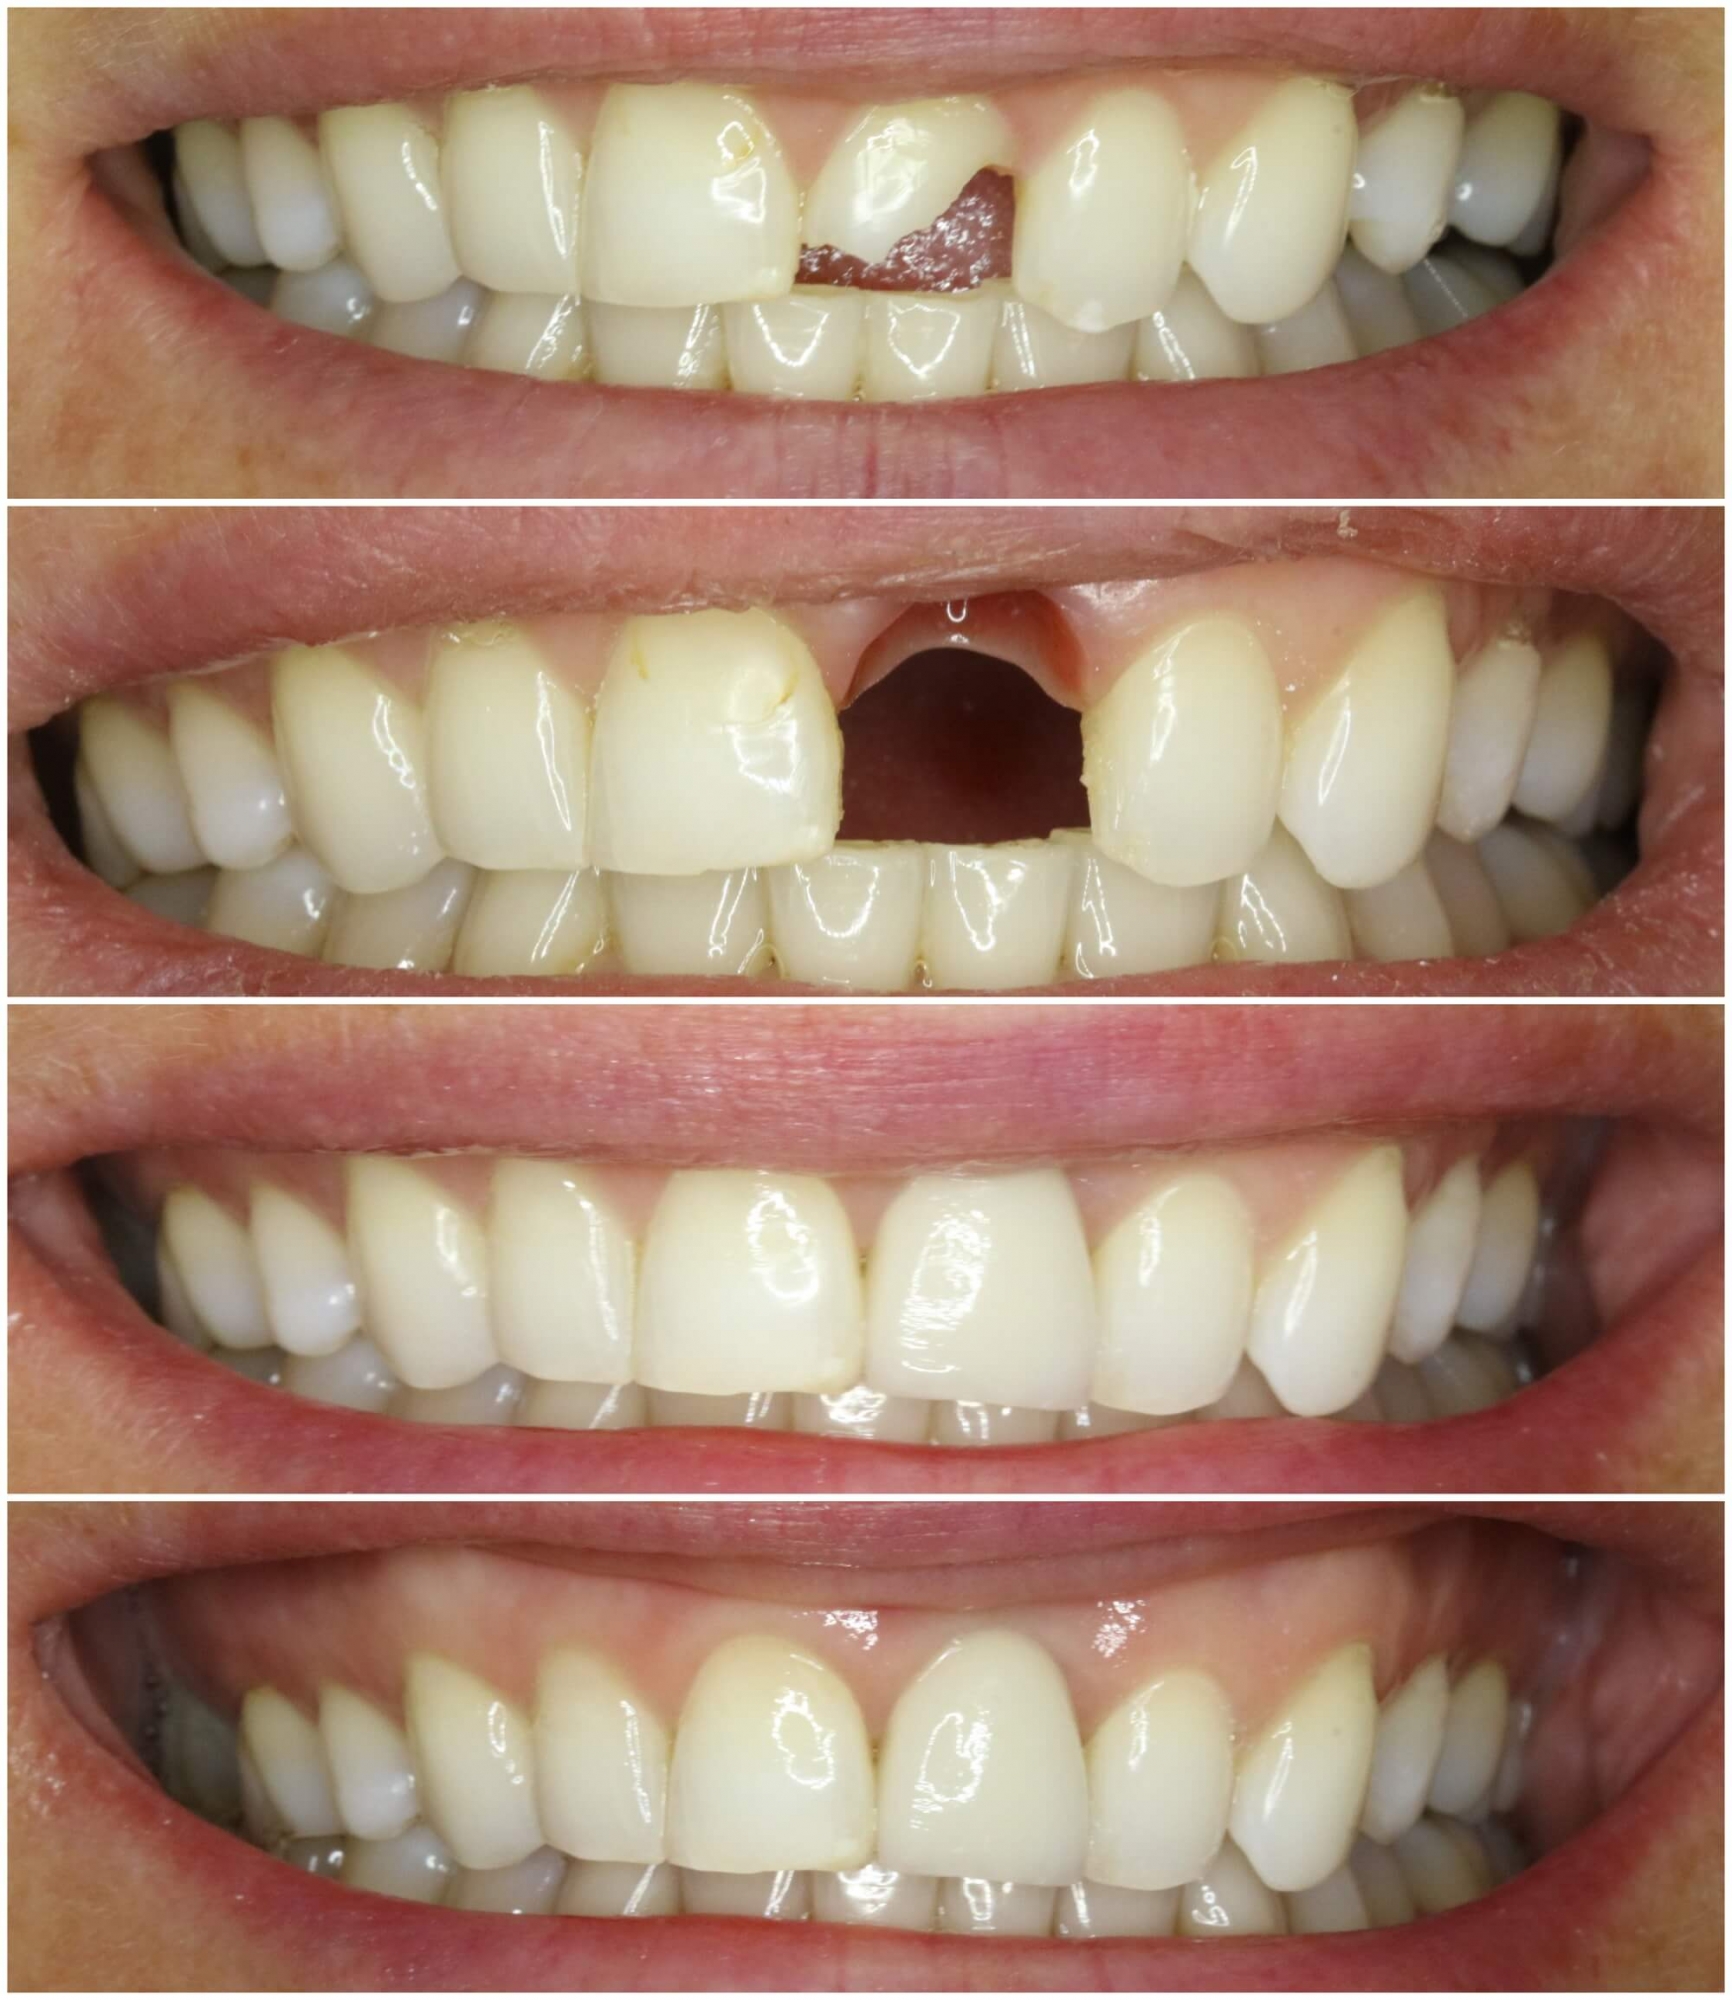

Slāņots cirkonija keramikas kronis + zoba implants

• Neatjaunojama zoba atraumatiska ekstrakcija (izraušana)

• Tūlītēja zoba implanta ievietošana un pagaidu kronīša (plastmasa) izgatavošana.

• Pēc 5 mēnešiem tika izgatavots slāņots cirkonijkeramikas kronis

• Tika  nomainītas vecās plombas priekšzobu rajonā